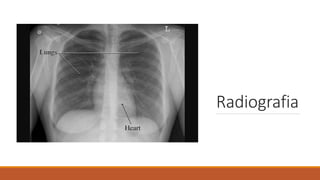

Radiografia

A imagem radiográfica aparece

quando há diferença de densidade

radiológica entre as estruturas

vizinhas do organismo.

Exemplo: na radiografia do tórax

aparecem ar (campos pulmonares),

partes moles e osso de maneira

distinta.

As radiografias são obtidas em pelo menos DUAS

posições padronizadas.

Exemplos:

Radiografia do tórax em PA (póstero-anterior) e Perfil

Radiografia do crânio em AP (anteroposterior) e Perfil.

Radiografia - Incidências

básicas

◦ Perfil ou latero-lateral:

◦ Os raios X atravessam o corpo no sentido

latero-lateral.

◦ No tórax, colocamos o lado esquerdo mais

próximo do filme, para que a imagem cardíaca

seja mais representativa do real.